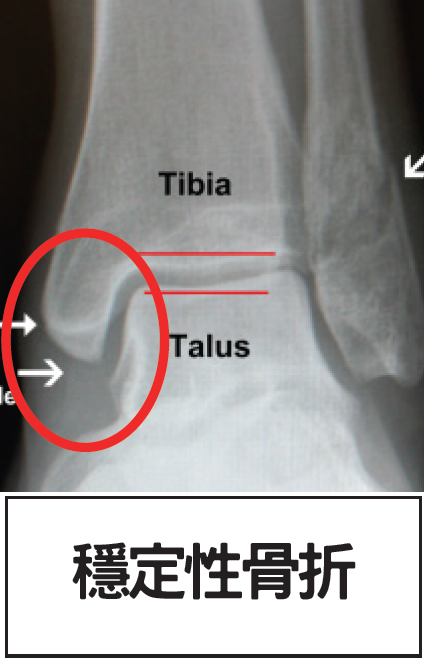

穩定性骨折: 若X光片上只見一條黑色骨裂線,而骨頭位置沒有移位(如下圖),多屬穩定性骨折。